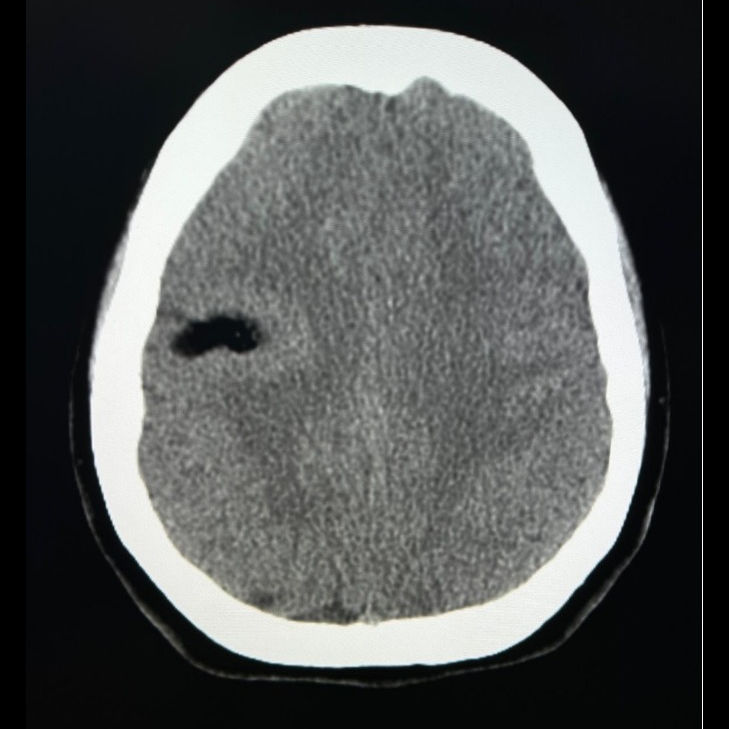

- A) Aksiyel kontrastsız BT’de lezyon yağ dansitesinde (-81HU) (kalın ok) izlenmekte olup lezyon etrafındaki korteks kalın görünümdedir (ince ok).

- BT’de düşük dansiteli kontrastlanmayan lezyon (−40 ila −100 HU)